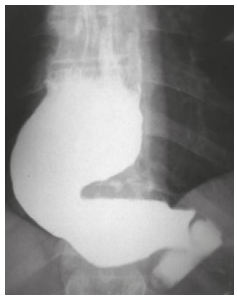

Mulher, 56 anos, portadora de megaesôfago grau IV (imagem abaixo). Admitida na enfermaria com desnutrição

grave. Após instalação de sonda nasoenteral e dieta, passou a apresentar exames laboratoriais compatíveis com

síndrome de realimentação.

Após realizar um ionograma, qual alteração foi identificada?